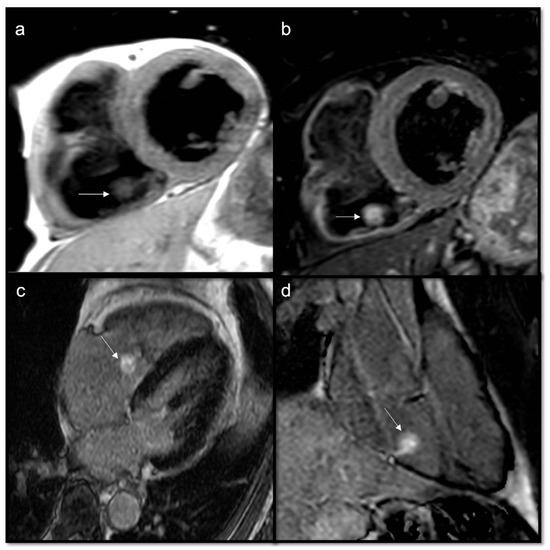

- To evaluate mobile masses, such as atrial myxomas or papillary valve fibroelastoma

- To reveal pericardial effusion

- Cardiac valve function and visualization of stenotic or regurgitant flow jets